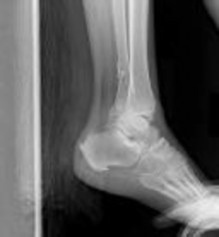

Figures 1 and 2 are the radiographs of a 68-year-old woman who comes to the emergency department after stepping into a hole and twisting her ankle. She is complaining of isolated ankle pain and is unable to bear weight.

After closed manipulative reduction and splint placement, she is scheduled for operative treatment. The stability of the syndesmosis should be evaluated after